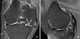

Degenerative osteoarthritis

Osteoarthritis (OA) is a type of joint disease that results from breakdown of joint cartilage and underlying bone. The most common symptoms are joint pain and stiffness. [Source: Wikipedia ]